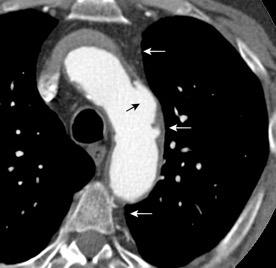

97. GANGLIOS CON CENTRO HIPODENSO

Tb ganglionar

31 años.. VIH+ C-3. Inmunosupresión severa. Tb miliar,ganglionar y pulmonar